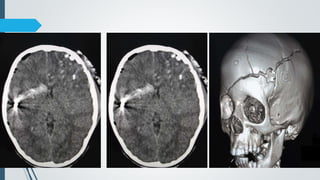

Diffuse axonal injury. CT scan demonstrates small hemorrhagic diffuse axonal injuries

in the deep white matter and corpus callosum.

Multiple hemorrhagic foci post MVA, involving the left thalamus and corpus callosum's splenium,

compatible with DAI.